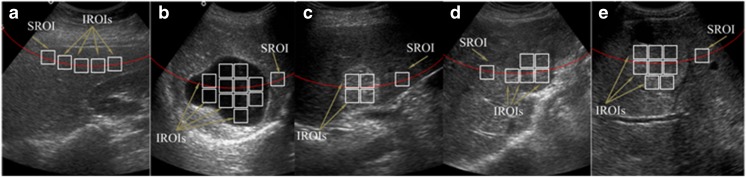

Two types of ROIs are used in this study, inside ROIs (IROIs) and surrounding ROIs (SROIs). For each Cyst, HEM, HCC and MET lesion maximum non-overlapping IROIs were cropped from well within the boundary of each lesion. The necrotic areas within lesions were avoided while cropping IROIs (as shown in Fig. 5e).

For each lesion, a single SROI was cropped from surrounding liver parenchyma approximately at the same depth as that of the center of the lesion by avoiding the inhomogeneous structures like liver ducts and blood vessels (as shown in Fig. 5b–e).

For each NOR image, a single extreme ROI is considered as SROI and all other ROIs at the same depth are considered as IROIs. SROIs and IROIs for NOR image were cropped by avoiding the inhomogeneous structures like liver ducts and blood vessels (as shown in Fig. 5a).

Fig. 5.

a–e NOR, Cyst, HEM, HCC and MET image with IROIs and SROI marked. Note: For NOR image, all IROIs and SROI are taken at the same depth. A single extreme ROI is considered as SROI. For liver images with lesions, SROI is extracted from background liver parenchyma surrounding the lesion approximately at the same depth as that of the center of the lesion by avoiding inhomogeneous areas like blood vessels and liver ducts. All IROIs are regions well inside the boundary of the lesions. As shown in e, necrotic area within the lesions is avoided while cropping IROIs

The sample image for NOR, Cyst, HEM, HCC and MET cases from the acquired image database with ROIs marked are shown in Fig. 5.

In the present work, two types of features are considered for analysis, i.e., texture features computed from IROIs and texture ratio features computed by taking the ratio of texture feature computed from IROI and texture feature computed from the corresponding SROI.

It can be noted that the NOR liver image in Fig. 5a contains four IROIs and a corresponding SROI; thus, four instances of the texture feature set and four instances of the texture ratio feature set are obtained. Similarly, from Cyst, HEM, HCC and MET lesions shown in Fig. 5b–e, 11, four, five and eight instances of the texture feature set and 11, four, five and eight instances of the texture ratio feature set are obtained.